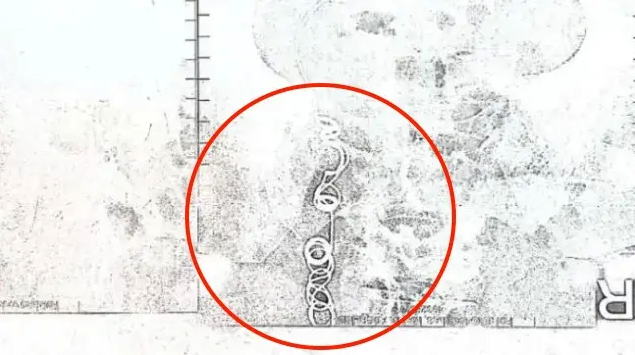

心力交瘁的她幾乎想放棄自己,直到2022年11月有醫生驚覺不對勁,認為這些症狀都太詭異了,決定請她進行核磁共振與超音波檢查,這一查所有人都傻眼了,在她體內竟存在手術用的針線,在醫生詢問下她恍然大悟,是結紮手術害了她10年之久!

艾德琳達崩潰表示:「我跟醫生都不敢相信眼前所見!」讓人傻眼的是,她去找當初幫她結紮的醫生,對方斬釘截鐵否認失誤,強調自己絕對不可能出現這樣的醫療疏失,還暗指是她自己將針線吞下肚。

面對這情況,專家憂心表示,異物長年留在體內是非常危險的事,嚴重的話還會導致癌症發生,艾德琳達只能等待醫生評估,確定她是否可以動手術將異物取出,然而發生這樣的事,白白受苦10年,真的希望最後的結果是好的啊!